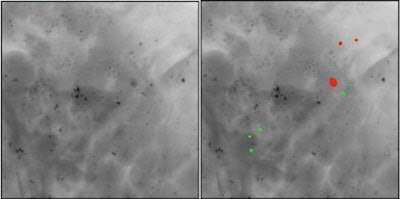

If confirmed, the new method would allow discrimination between type I (green) and type II (red) microcalcifications in a noninvasive way.The method relies on the observation that some microcalcifications show opposite absorption and small-angle scattering signals. The novel technique is highly sensitive to the morphological and structural information of the microcalcifications, where conventional absorption-based x-ray mammography is not.

Stampanoni's presented hypothesis assumes that for any given microcalcification thickness, one type gives a weaker absorption signal, but a stronger small-angle scattering signal, than the other. Type I microcalcifications generally show a smaller attenuation signal and are crystalline in nature, whereas type II are not. Therefore, type I microcalcifications are expected to give a higher scattering signal than type II.